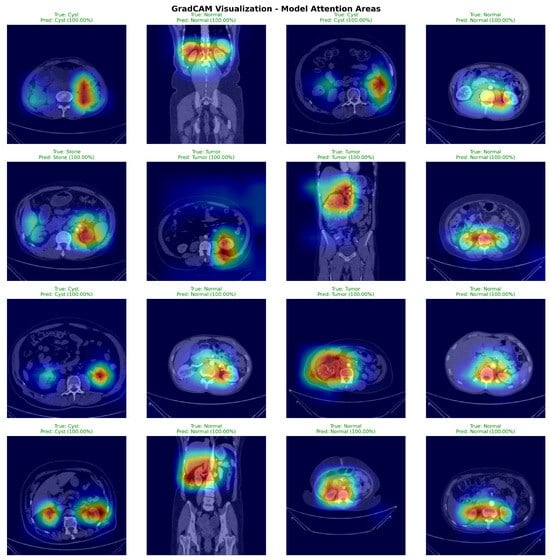

4.3. Attention Visualization and GradCAM Analysis

Figure 7 presents GradCAM visualizations demonstrating DiagNeXt’s ability to focus on clinically relevant regions. The attention maps reveal that the model successfully identifies and highlights pathological areas while ignoring irrelevant background regions.

Figure 7.

GradCAM visualizations from 50 randomly selected test set cases (12–13 per pathology class). Sample selection ensured balanced class representation. Warmer colors (yellow–red) indicate regions with higher model attention and stronger contribution to the predicted class, while cooler colors (blue–green) correspond to low-importance areas.

The visualizations demonstrate several key insights:

- For Cysts: The model focuses on the characteristic hypodense, well-circumscribed lesions with smooth borders;

- For Tumors: Attention concentrates on heterogeneous enhancement patterns and irregular margins typical of renal cell carcinoma;

- For Stones: The model highlights high-density calcifications and associated inflammatory changes;

- For Normal tissue: Attention is distributed across normal parenchymal architecture without focal abnormalities.